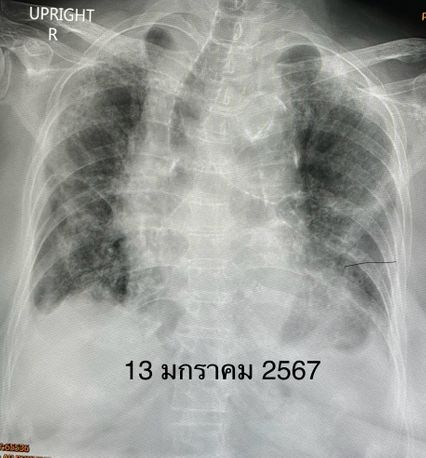

แพทย์วินิจฉัยว่า ปอดอักเสบจากไวรัสโควิด-19 ให้เข้านอนรักษาในโรงพยาบาล เมื่อวันที่ 14 ธ.ค.66 ให้ออกซิเจน 6 ลิตร/นาที ให้ยาฉีดเรมเดซิเวียร์และยากินแพ็กซ์โลวิดพร้อมกัน 5 วัน และยาสเตียรอยด์ คนไข้ดีขึ้นช้าๆ แพทย์ให้กลับบ้านได้ในวันที่ 24 ธ.ค.66 (รักษานาน 10 วัน) หลังกลับบ้านเพียง 1 วัน ผู้ป่วยมีอาการเหนื่อย และมีไข้ขึ้นอีก ตรวจ ATK ให้ผลลบ แต่ผลส่งตรวจรหัสพันธุกรรมยังพบไวรัสโควิด-19 เอกซเรย์ปอดมีฝ้าขาวเพิ่มขึ้น และปอดขนาดเล็กลง

การรักษาในรอบที่ 2 แพทย์วินิจฉัยว่าไวรัสโควิด-19 ยังอยู่ในปอดก่อให้เกิดปอดอักเสบและพังผืดในปอด ให้ออกซิเจน 6 ลิตร/นาที ให้ยาต้านไวรัส 3 ชนิดพร้อมกัน คือยาฉีดเรมเดซิเวียร์ ยากินแพ็กซ์โลวิด และโมลนูพิราเวียร์นาน 5 วัน และให้ยาสเตียรอยด์ ทำคอมพิวเตอร์ปอดเห็นปอดขนาดเล็กลง มีฝ้าขาวพังผืดทั้ง 2 ข้าง มีถุงลมพองและพังผืดดึงรั้งให้หลอดลมโป่งพอง มีน้ำในเยื่อหุ้มปอดเล็กน้อย ทำอัลตราซาวด์หัวใจEchocardiogram พบความดันของหลอดเลือดแดงในปอดปกติ คนไข้ดีขึ้น เหนื่อยน้อยลง เอกซเรย์ปอดดีขึ้นช้าๆ ลดการให้ออกซิเจนลงได้เหลือ 2 ลิตร/นาที แพทย์ให้กลับบ้านได้วันที่ 8 ก.พ.67